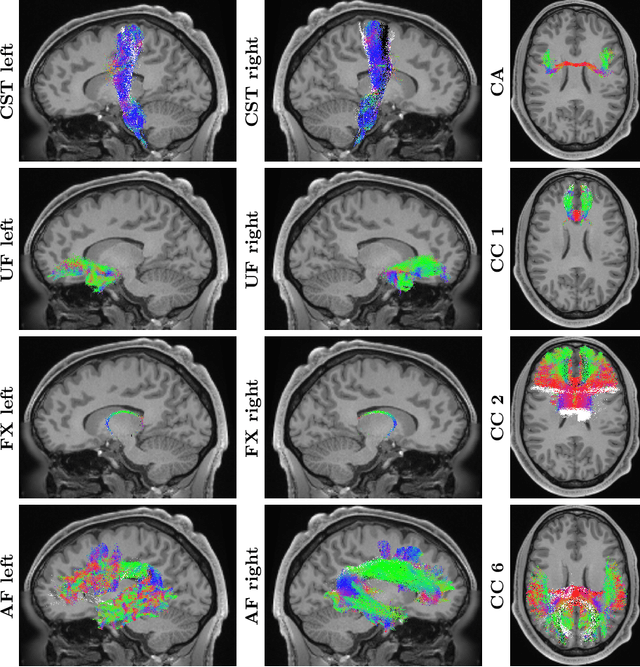

Abstract:Parcellation of whole-brain tractography streamlines is an important step for tract-based analysis of brain white matter microstructure. Existing fiber parcellation approaches rely on accurate registration between an atlas and the tractograms of an individual, however, due to large individual differences, accurate registration is hard to guarantee in practice. To resolve this issue, we propose a novel deep learning method, called DeepBundle, for registration-free fiber parcellation. Our method utilizes graph convolution neural networks (GCNNs) to predict the parcellation label of each fiber tract. GCNNs are capable of extracting the geometric features of each fiber tract and harnessing the resulting features for accurate fiber parcellation and ultimately avoiding the use of atlases and any registration method. We evaluate DeepBundle using data from the Human Connectome Project. Experimental results demonstrate the advantages of DeepBundle and suggest that the geometric features extracted from each fiber tract can be used to effectively parcellate the fiber tracts.